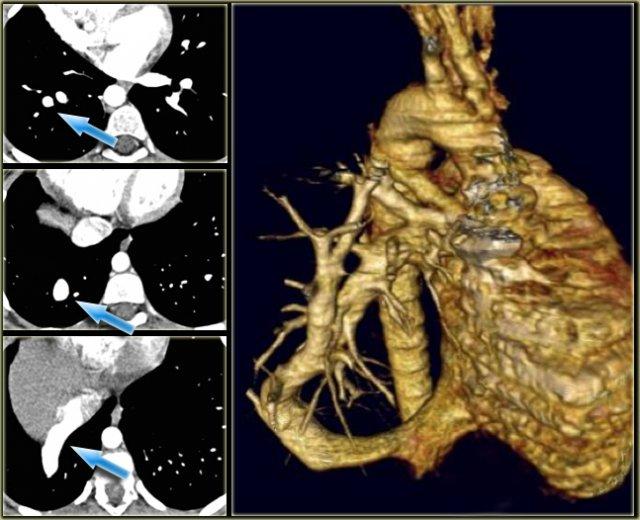

Azygos Continuation of IVC

- Abcense of hepatic segment of IVC with azygos continuation.

- IVC interrupted above level of renal veins.

- Association with congenital heart disease and polysplenia.